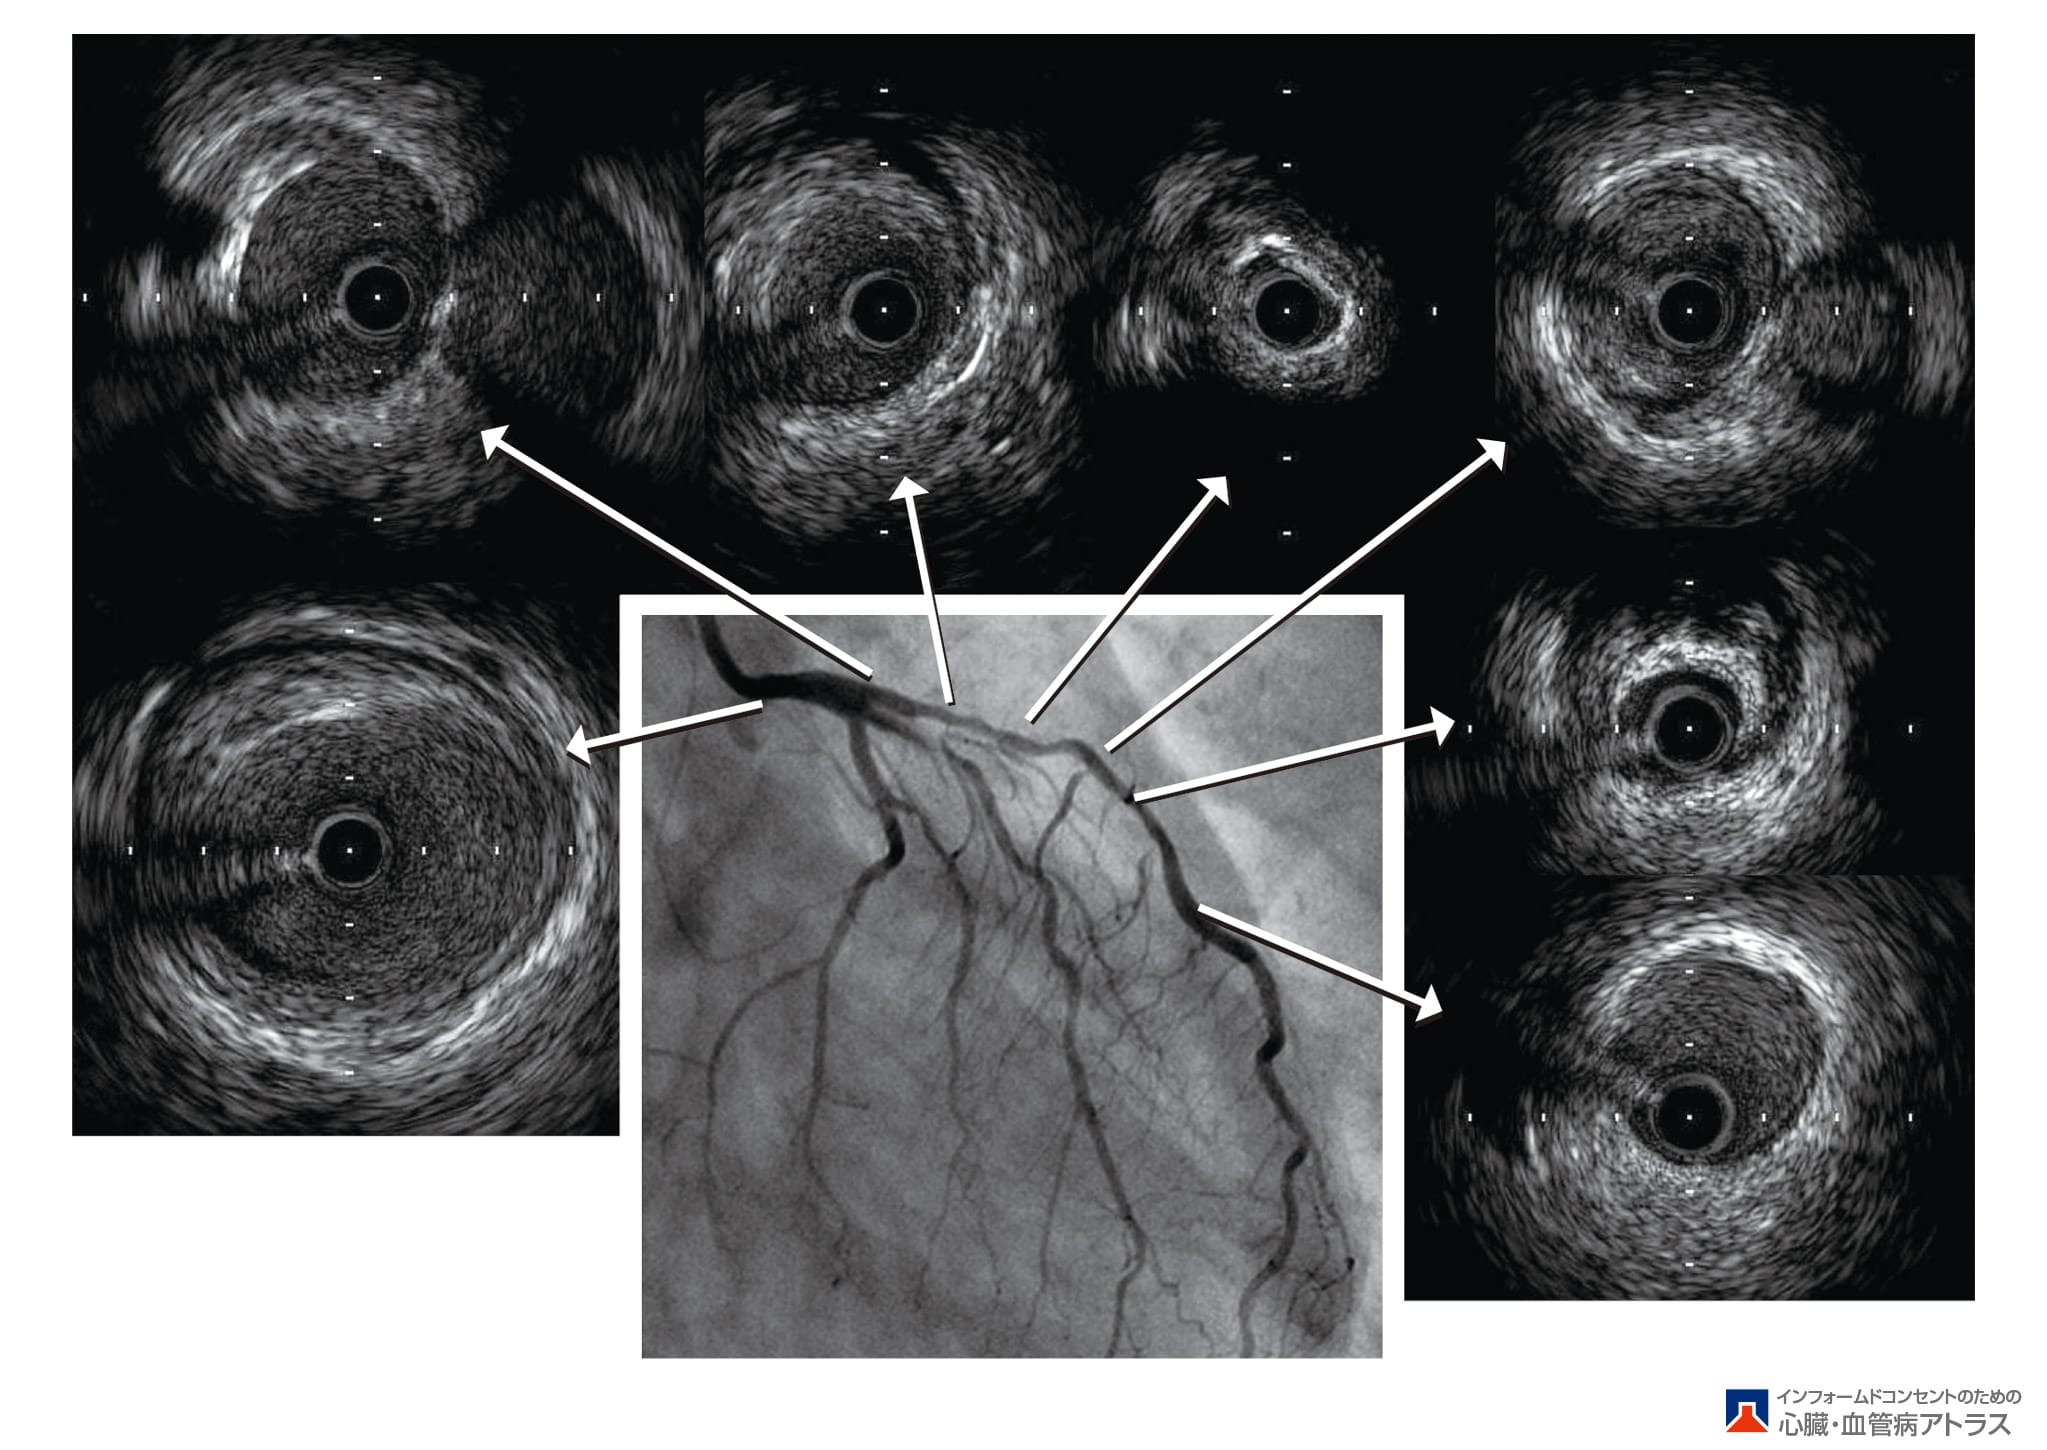

- 心臓の検査:継続的なエステの手続き、心臓から心臓への血液検査。コラソンの筋肉と軍医の医療機関の検査、または血管の検査を許可します。